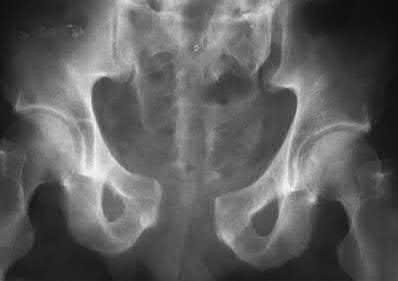

A poly-trauma patient presents hemodynamically unstable with an anteroposterior compression (APC-III) pelvic ring injury. A circumferential pelvic binder is requested to reduce pelvic volume and control hemorrhage. To be anatomically effective, the binder must be centered precisely over which of the following landmarks?

For optimal mechanical advantage and effective reduction of an 'open book' pelvic fracture (APC type), a pelvic binder must be applied directly over the greater trochanters of the femurs. Applying it higher, such as over the iliac crests, is a common error that fails to adequately close the pelvic ring and can paradoxically open the true pelvis.